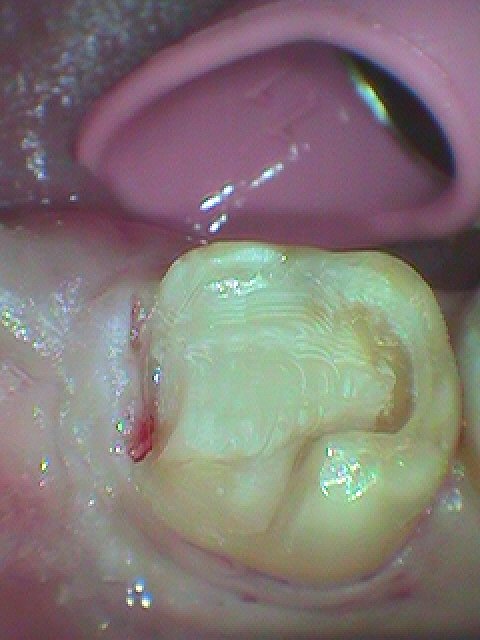

中は大きく虫歯になっていました

深部にまで虫歯が進行していました

CR樹脂にて覆罩を行っています